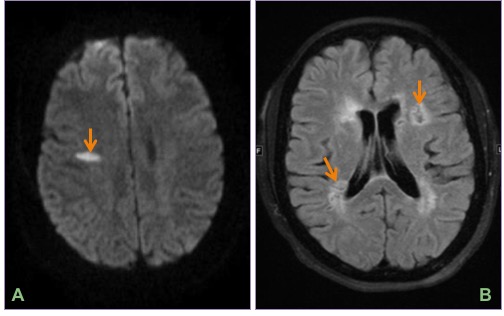

Axial DWI (A) and FLAIR (B) images show an acute infarct in the right centrum semiovale and multiple remote infarcts in bilateral periventricular white matter.